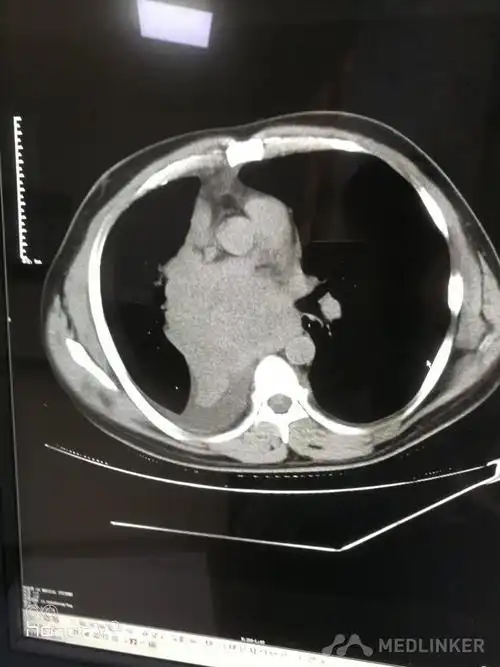

1例左下肺中央型鳞癌患者,斜裂不发育,肿瘤侵犯下叶支气管和上叶舌段